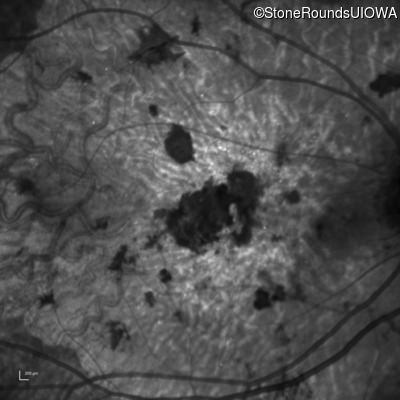

Infrared Fundus Photograph - Left - 20/300 sc

Exemplar